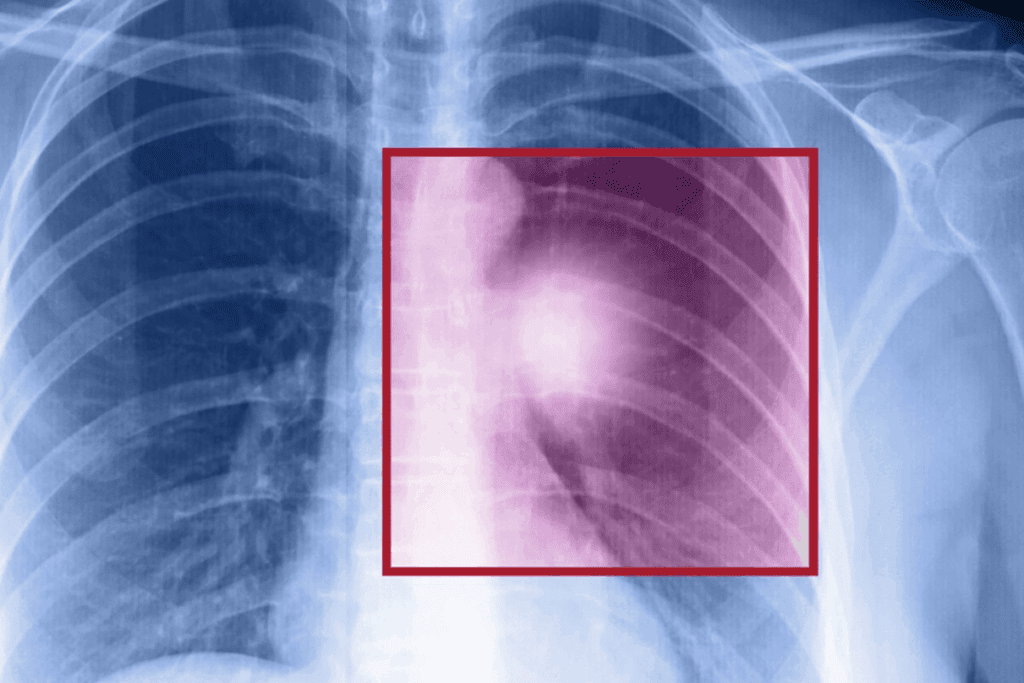

Ribs Broken for Lung Surgery: The Truth

The idea that ribs are always broken during lung surgery is not true. Lung surgery, or thoracic surgery, includes many procedures. These may need different ways to open the chest.

A study in the Journal of Trauma and Acute Care Surgery showed rib fractures are common in lung surgery, mainly in older people. This shows why keeping the ribs safe is key in planning surgery. Doctors now think about the patient’s health, the condition, and the best surgery method to reduce risks.

Even with new techniques, sometimes breaking ribs is needed. If a tumor is big or touches the chest wall, a bigger surgery might be required. The choice to break or remove ribs depends on the patient’s situation and what’s best for them.